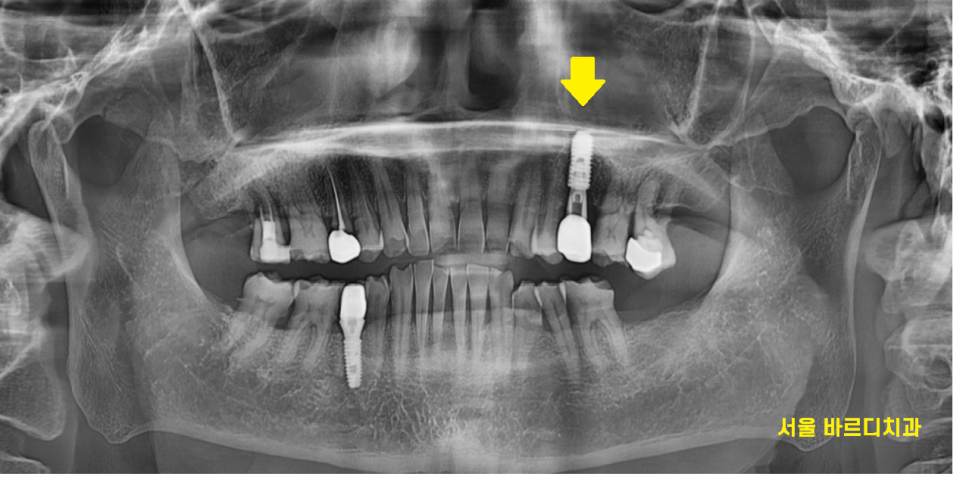

오래전 하셨던 금니 보철물이 빠져

내원한 환자분입니다.

금니 빠짐 부위가 치아와 함께

부러졌네요ㅠㅠ

치아 부러진 부위가 너무 커서

발치할 수 밖에 없었는데요.

23.11.14

치아가 부러져서 뽑는 경우에는

잇몸뼈가 좋기 때문에

바로 임플란트를 심어드렸습니다.

금니 빠짐으로 내원하셨고

임플란트 치료로 완료해드렸습니다.